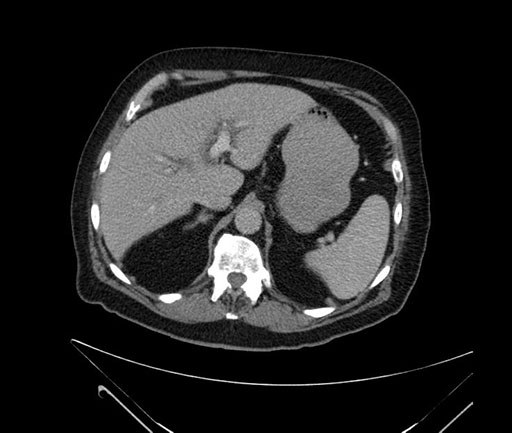

Whipple (pancreaticoduodenectomy) [case 7]

Axial - stented